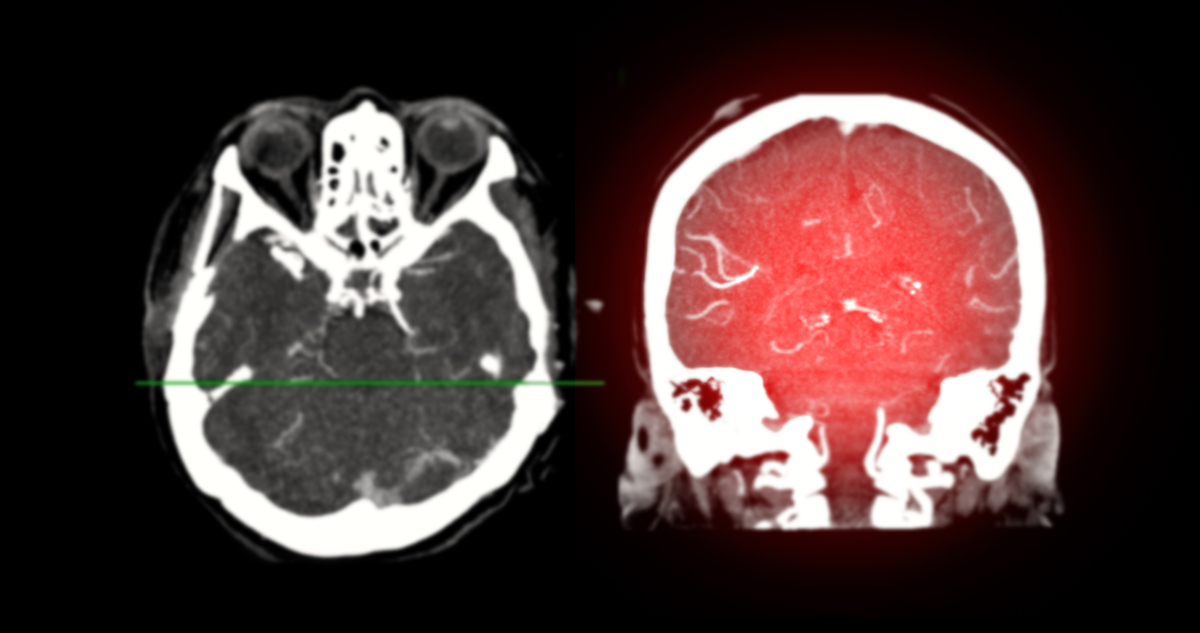

右侧颈内动脉起始部中度狭窄伴漂浮血栓形成:DSA、CTA、MRA诊断

脑部DSA、CTA及MRA检查均证实患者右侧颈内动脉起始部存在中度狭窄,并伴有漂浮血栓形成。